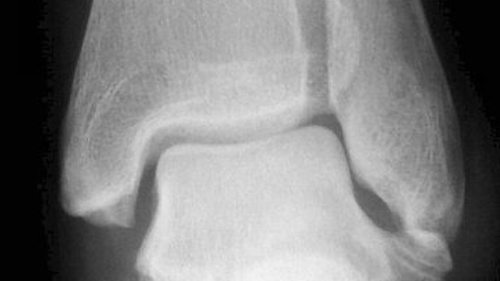

Mais voilà, le jour où je suis allé enlever mon plâtre, il ont montré pour la première fois mes radios au chef de clinique. Et voilà que celui-ci me dit qu’il n’ont malheureusement mal vu, mais ma malléole était déplacée et qu’il auraient dû opérer.

Mais bon, maintenant c’est trop tard. Par “chance” l’articulation est bonne, il va juste falloir plus de temps pour que cela se consolide.